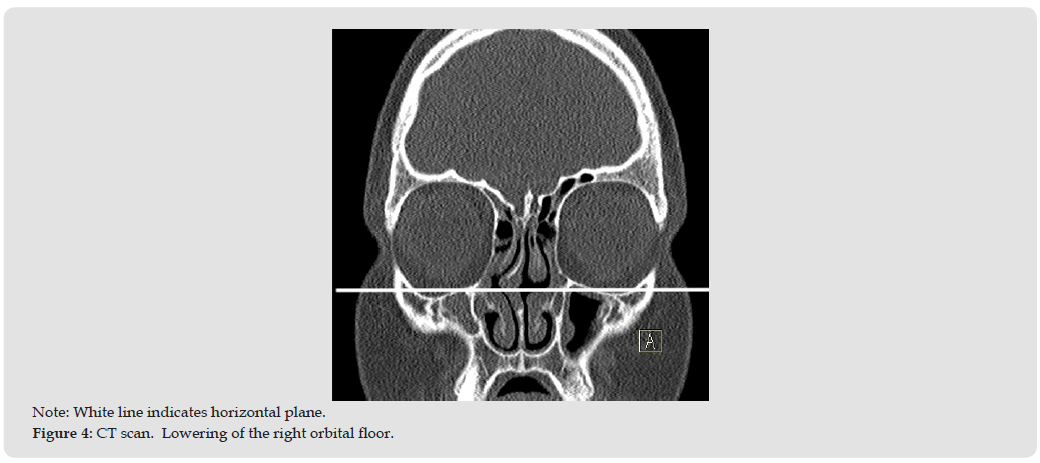

A 14 - year-old boy with chronic nasal congestion presented at the hospital because of diplopia and impaired visual acuity in the right eye. A CT scan of the sinuses showed asymmetry of the maxillary sinuses with a significant reduction in the volume of the right maxillary sinus. A total opacification of the right maxillary sinus with inward bowing of its medial wall was present (Figures 4 & 5). There was also lowering of the right orbital floor shown (Figure 4). The child was qualified for an endoscopic sinus surgery. The endoscopy showed a displaced lateral wall of the nose to the right. The lateralization of the uncinate process with its adhesion to the lateral wall was observed (Figure 5). The gentle luxation of the uncinate with a ball probe and its removal was performed. The sinus opening was located and widened. Thick discharge was found inside the maxillary sinus. Multiple rinsings were performed. The mucosa of the right maxillary sinus was slightly swollen. No complications were observed in the perioperative period.